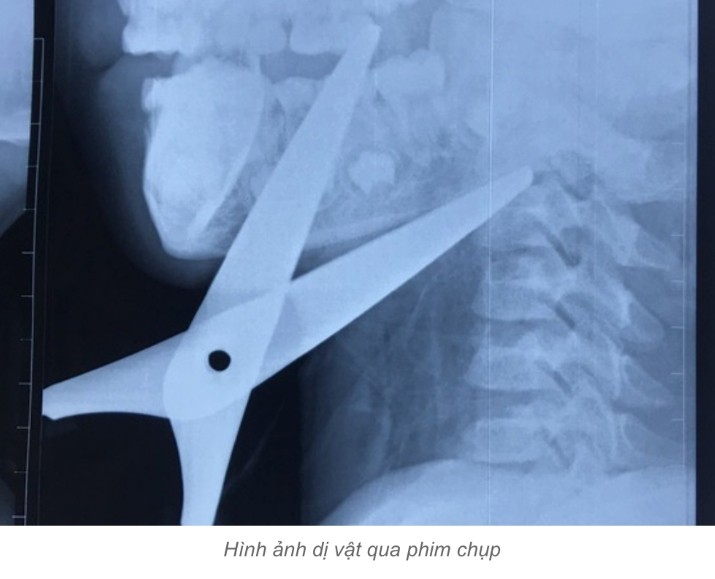

Báo Người Lao Động cho biết thêm, hình ảnh phim chụp cho thấy 2 mũi kéo đi theo 2 hướng khác nhau vào vùng góc hàm sàn miệng và đi xuyên qua hệ thống mạch máu, thần kinh, dừng lại khi cắm vào thân đốt sống cổ C2. Lưỡi kéo chạy sau nằm sát động mạch cảnh trong bên phải. Bệnh nhi được chỉ định mổ cấp cứu.

Ca phẫu thuật kéo dài 2 giờ và kíp mổ đã lôi được dị vật ra khỏi cơ thể bệnh nhi, các mạch máu, cơ và thần kinh tổn thương được khôi phục, cháu có thể ra viện trong vài ngày tới.